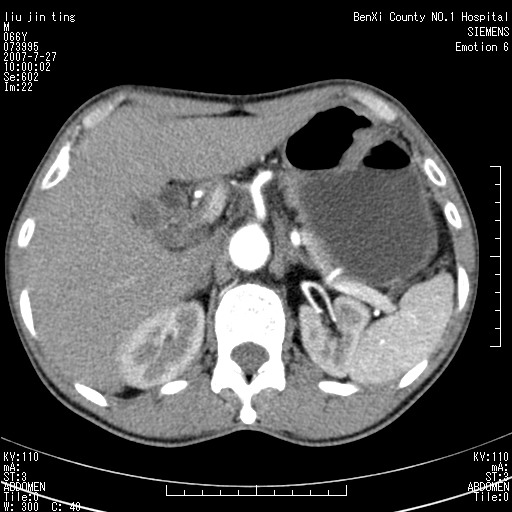

腹痛,背痛,无恶心呕吐,不黄,彩超示胰腺钩癌,ct扫描病灶平扫30-40hu,增强后动脉期40--60hu,静脉期50-68hu,真的是钩突上的么?您要试一试么?

动脉期

静脉期

沿着肠系膜上动脉呈匍匐性生长的软组织肿块,形态不规则,包绕肠系膜上动脉,呈明显强化,考虑来源于肠系膜的恶性肿瘤

沿着肠系膜上动脉呈匍匐性生长的软组织肿块,形态不规则,包绕肠系膜上动脉,呈轻-中度强化,考虑来源于肠系膜的恶性肿瘤。

钩突是正常的,只见腹膜后淋巴结的肿大,考虑淋巴瘤或转移可能。